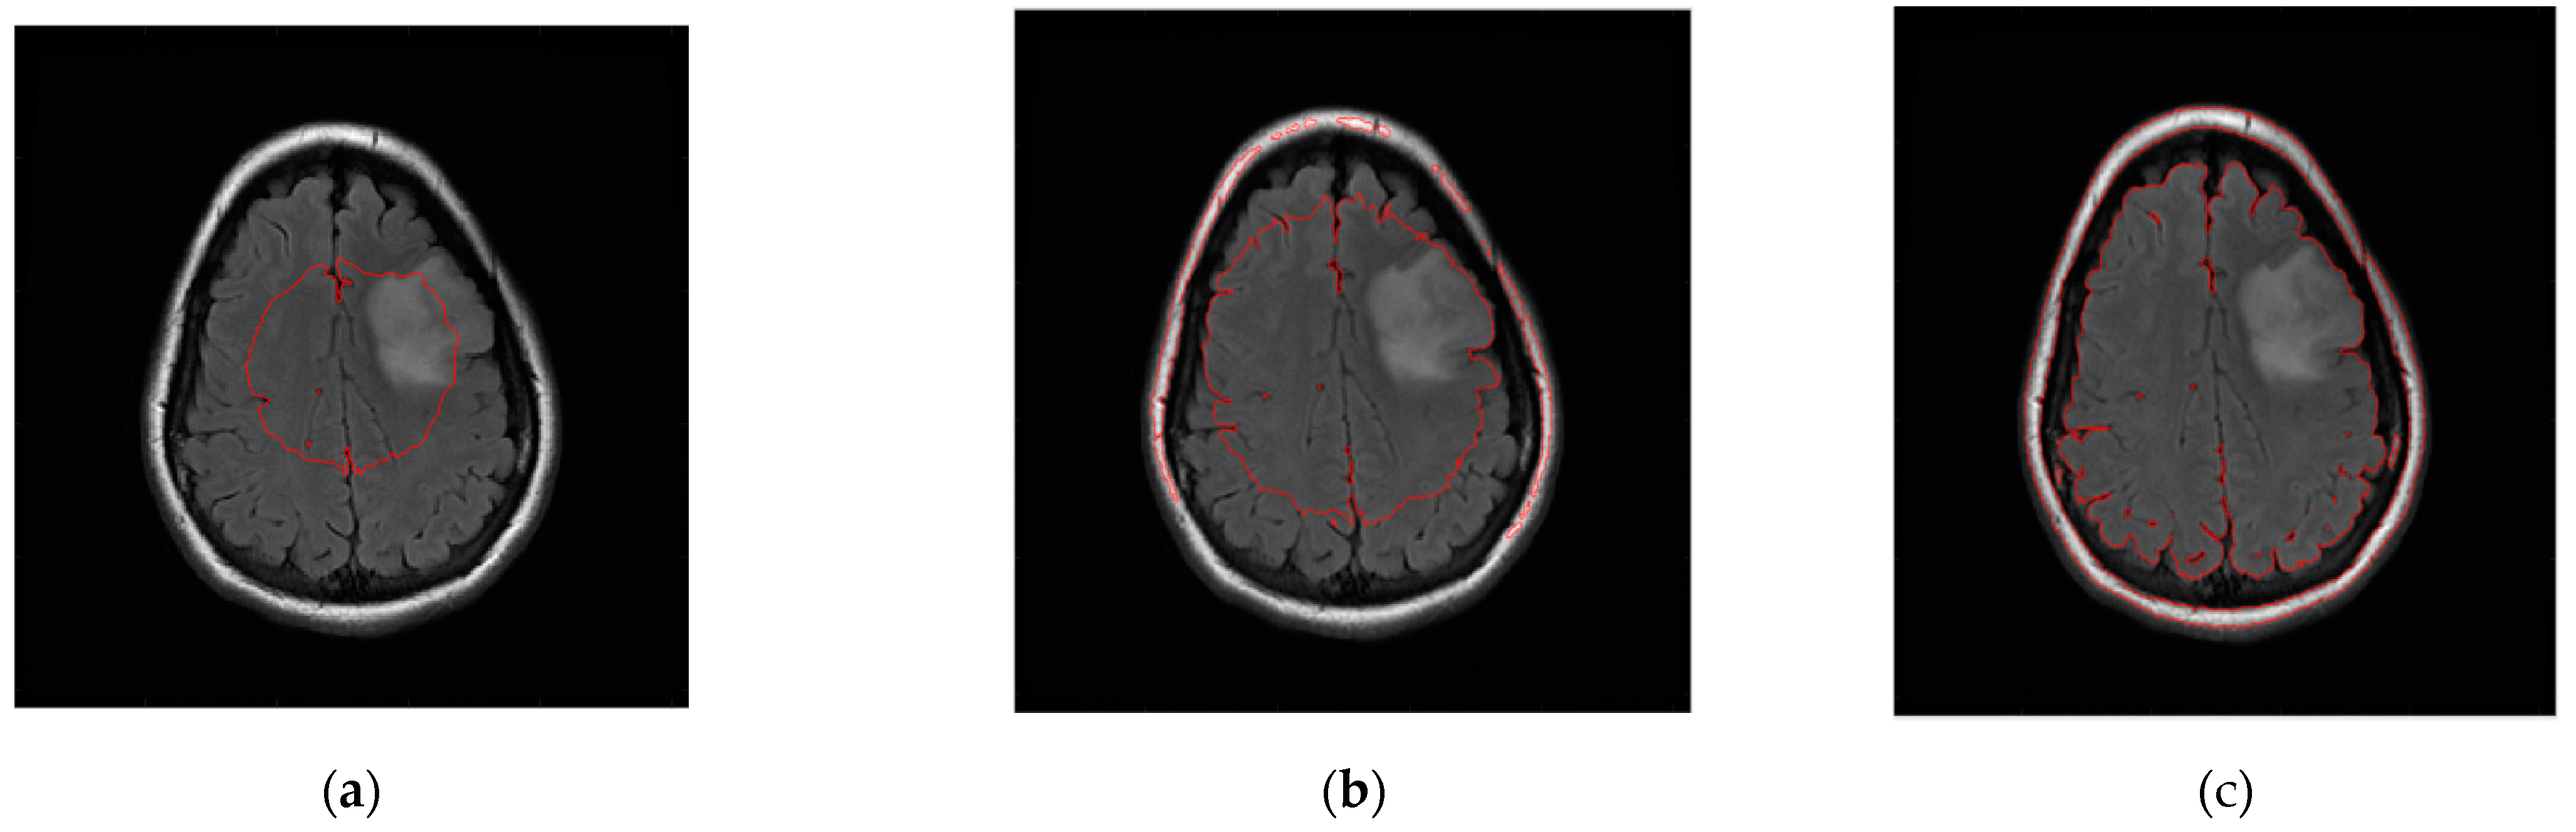

The level set initialization is required to segment the image by the CV model, and the average gray values c1 and c2 of the foreground and background are initially estimated according to the initialized level set. Then, each point on the level set is updated through the evolution equation. If the gray value of the current point is close to the gray average value of the foreground, the value of the corresponding level set of this point increases, otherwise it decreases. In CT and MRI images, the grayscale difference between brain tumors and background images is very small, and the boundaries are blurred. It is difficult to achieve satisfactory segmentation when directly applying the CV model to cross-sectional images for brain tumor detection. As shown in Figure 6, the CV model fails to converge to the location of the brain tumor.

Figure 6.

Brain tumor segment by CV model under different numbers of iterations. (a) 50 iterations. (b) 300 iterations. (c) 1000 iterations.

After locating the unit area where the tumor is located in Section 2.2, we can segment the tumor tissue through the improved CV model, so that the tumor tissue can be accurately detected and segmented, as shown in Figure 7.

Figure 7.

The improved CV model detection.